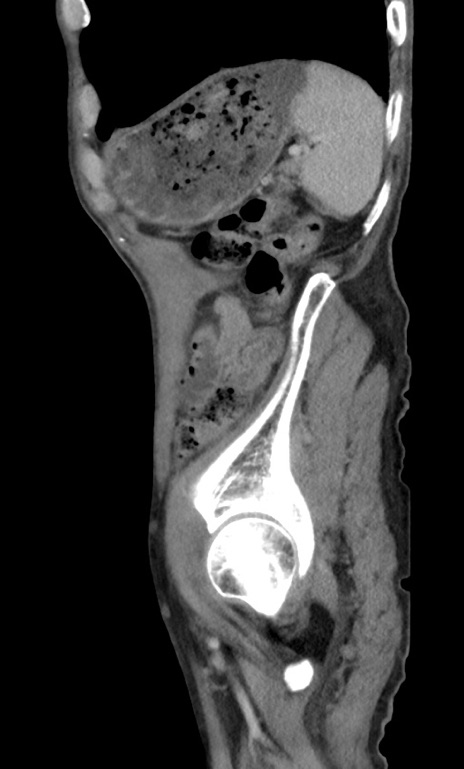

症例3(矢状断像)

【症例】 70歳代男性

【主訴】右鼠径部腫瘤、疼痛

【現病歴】本日朝より上記主訴あり、受診。

【既往歴】膀胱癌にて膀胱全摘、両側尿管皮膚瘻

【データ】WBC 5600、CRP 0.56